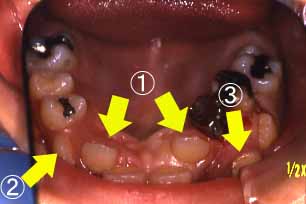

正面

下顎

(ミラー像)

C右下4番目の歯がひっかか

っている。